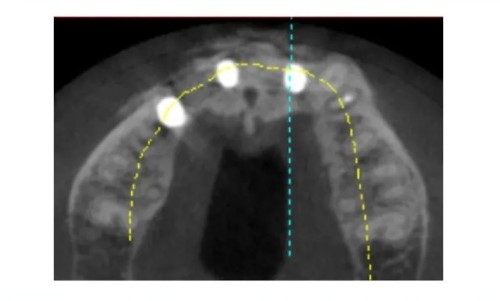

Three-dimensional reconstruction: Bone deficiency observed in the labial wall near the mesial aspect of A4 and on the buccal side of A3, while the lingual wall remains intact. Adequate bone volume is observed for A2 and B2.

Extensive bone destruction is observed in A3, leading to bone deficiencies in A4 and A2.

Due to bone deficiency in the distal aspect of A2, the design is modified to place the implant in the A1 region, avoiding the area of bone deficiency.

Extensive bone destruction is observed in A3, resulting in bone deficiencies in A4 and A2.

It is observed that the buccal-lingual bone width is adequate in the A1 region.

It is observed that the buccal-lingual bone width is adequate in the B2 region.